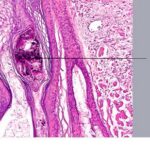

Because not all follicles in a given area are affected, transversely sectioned scalp biopsies may increase the yield of finding the diagnostic histologic features of trichotillomania, including increased numbers of catagen and telogen hairs (most cases) and empty or distorted follicles (greater than 50% of cases) (194). The same study found pigment casts and trichomalacia in less than 50% of cases. When the scalp is also rubbed persistently, epidermal changes of lichen simplex chronicus may be seen in vertical sections. |

being deposited distally as the hair is plucked {194}. Pigment casts are due to injury to the hair matrix, although some authors have theorized that they result from the sudden conversion of anagen to catagen . Hair shaft changes, termed trichomalacia, may be seen. Characterized by diminished size, distorted and odd shape, and irregular pigmentation of the shaft, trichomalacia is additional evidence of trauma to the matrix . Traumatized follicles can also show considerable distortion of the bulbar epithelium and conspicuous hemorrhage . |

Pigment casts, which are clumps of melanin pigment, may be seen in the hair papilla and peribulbar connective tissue. They are also commonly seen in the upper portion of the hair follicle as a result of pigmented matrical cells |

Histopathology. In horizontally sectioned biopsies of trichotillomania uncomplicated by the coexistence of other types of alopecia, the density of hair follicles is normal, as is the terminal-to-vellus hair ratio. The diagnostic finding, when seen, is distorted hair follicle anatomy, without inflammation . Specifically, the pulling of hairs can leave behind empty anagen follicles and "torn-away" follicles, the result of plucked hair shafts that retain parts of the hair matrix and root sheaths . Additional microscopic evidence of traumatic injury was published by Royer et al. as the "hamburger sign," describing a vertically oriented split in the hair shaft containing proteinaceous material and erythrocytes, resembling a hamburger within a bun . Damaged follicles enter the resting phase, leading to an increase in the percentage of catagen and telogen hairs, as high as 75% . Often the hairs do not become normal catagen hairs and appear distorted and abnormal . |